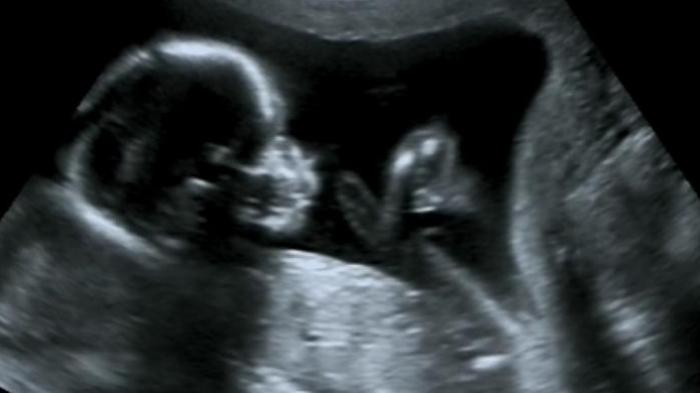

TRIBUNJABAR.ID - Terungkap, ada sebuah klinik atau praktik aborsi ilegal di wilayah Paseban, Jakarta Pusat.

Praktik aborsi tersebut bahkan telah melakukan tindakan ilegal itu kepada 1.632 pasien dan menggugurkan janin dari 903 pasien.

Polda Metro Jaya mengungkap praktik aborsi ilegal Paseban pada 11 Februari 2020.